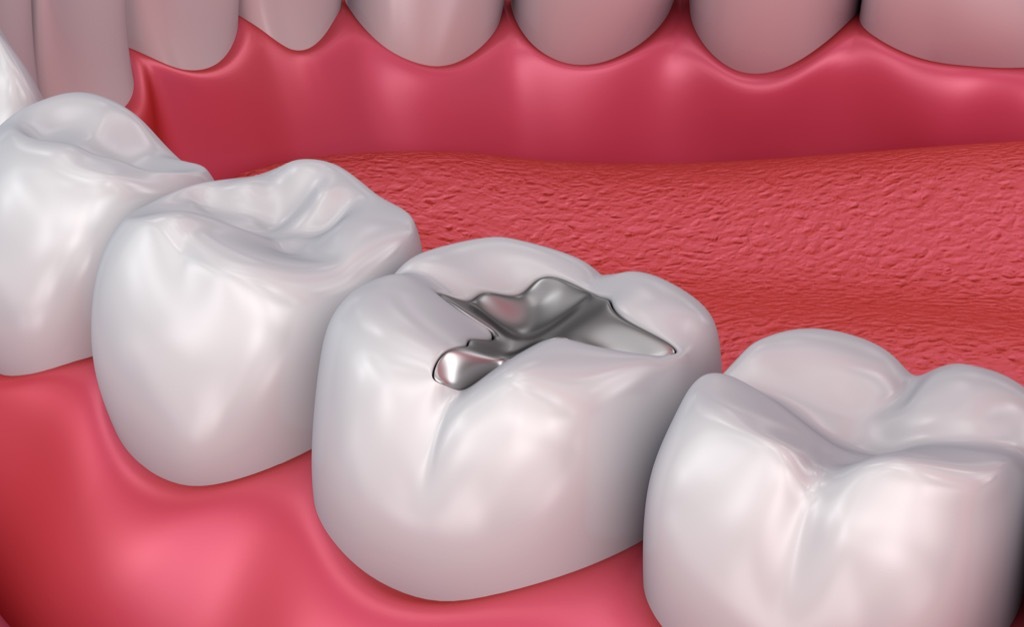

11 Metallfüllungen dauern länger

Zahnärzte machen typischerweise einen guten Fall für eine gute Art der Füllung, auf die sie sich spezialisiert haben, indem sie einige der umgebenden Details auslassen. Eine Information, die nicht erwähnt werden darf, ist, dass Metallfüllungen im Gegensatz zu Keramik im Gegensatz zu den Jahren dauerhaft sind.